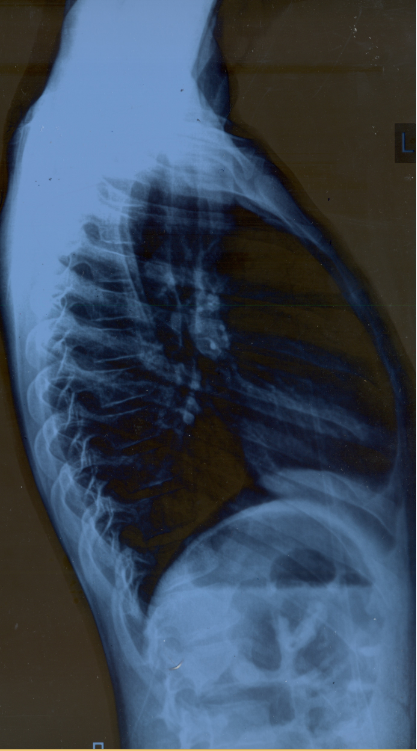

My son ribs bone structure is de-shaping. It's Pectus Carinatum case. Sheikh Zayed Dr. asked to use maximum milk and calcium products in May,2019 but issue is not getting resolved. Kindly advise.

there is possibility that your son is suffering from Rickets or some metabollic deficiency, his clinical examination may reveal some other findings as wel

we have to check for ribs and spinal joints. please bring him to us for detailed evaluation and possible treatment